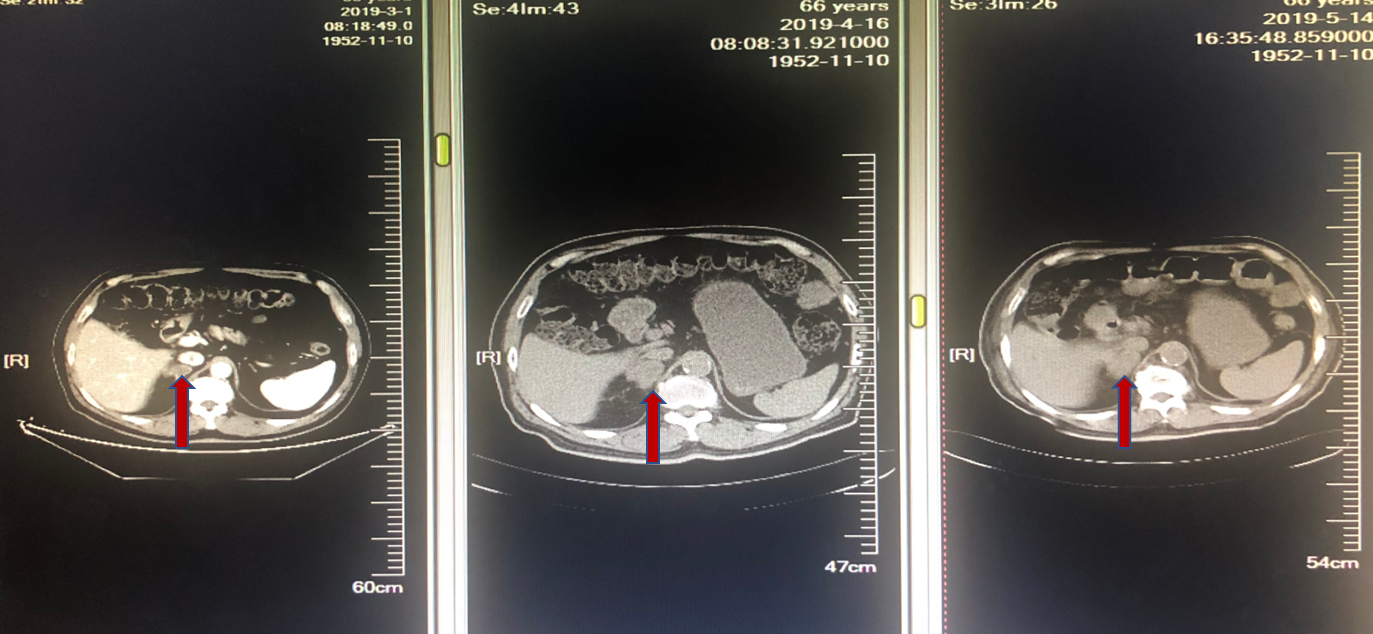

2019年2月至4月行DP方案化疗,方案为多西紫杉醇120mg + 奈达铂 120mg x 2周期。2周期治疗后评估,咳嗽咳痰带血未见改善,出现腰部疼痛。病灶增大,出现骨转移,评估疾病PD。

图3. 一线化疗2个周期后复查

图4. 一线化疗2个周期后复查新发骨转移

2019年5月更换为GP方案化疗,具体方案为吉西他滨1400mg + 顺铂 100mg x 1周期。同时接受唑来膦酸4mg x 1周期。化疗期间患者咳血胸闷加重,且周身乏力不适症状明显,急诊入院。1周期化疗后咳嗽咳血加重,腰部疼痛未缓解。复查胸部CT,右肺上叶病灶PD;右肾上腺病灶SD。患者对治疗耐受差,总体评价为PD。

图5. 二线化疗1周期后评估,右肺上叶病灶PD

图6. 二线化疗1周期后右肾上腺病灶评估SD